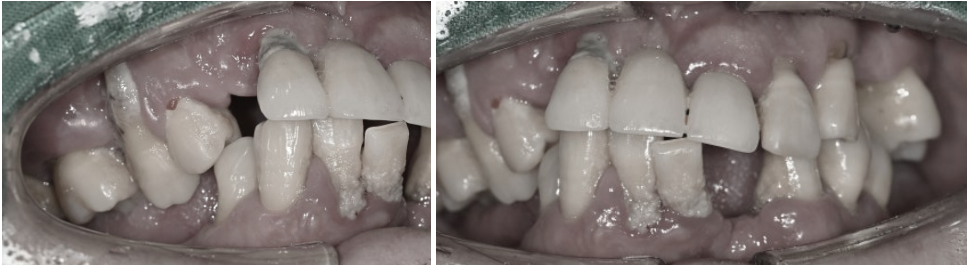

당뇨 질환과 오랜 흡연과 더불어

구강 관리 상태가 아쉽습니다.

당뇨와 흡연은

치주염의 위험을 높이는

원인이기 때문에

임플란트를 안정적으로

마무리하기 위해선

둘 다 조절하는 과정이

필수랍니다.

앞서 말씀드렸던 관리 영역으로,

다량의 치태와 치석이

여러 군데 침착되어 있습니다.

양치나 치실 등

구강 관리가 미비한 것으로 보입니다.